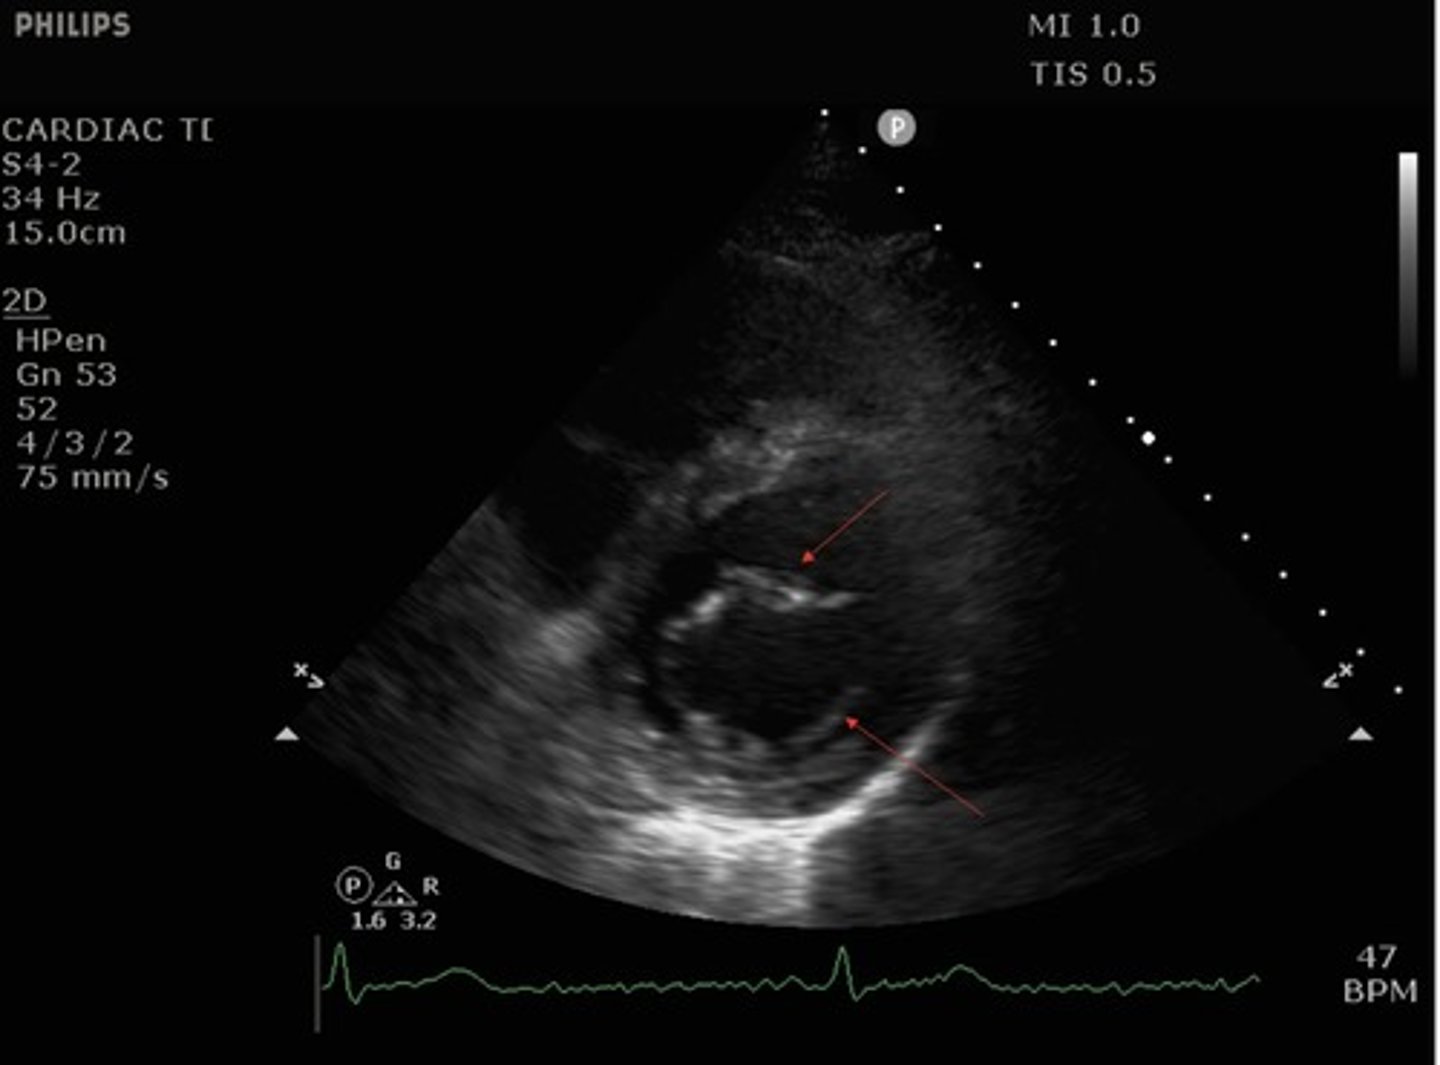

parasternal short axis mitral valve view

what view is this?

top arrow: anterior leaflet of mitral valve

bottom arrow: posterior leaflet of mitral valve

What structures are indicated by the red arrows?